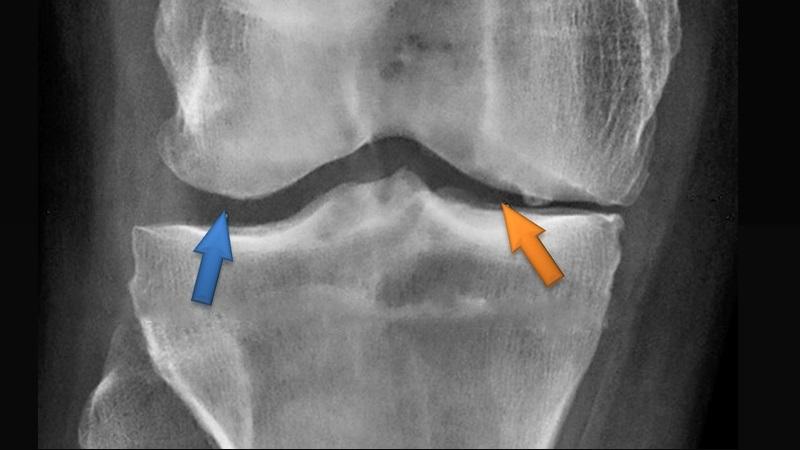

На основе клинических симптомов и опроса пациента проводятся диагностические исследования для выявления маркеров остеопороза: плотности костей, скрытых переломов и деформации хрящей. Диагностика осуществляется с помощью денситометрии, МРТ, КТ и рентгенографии.